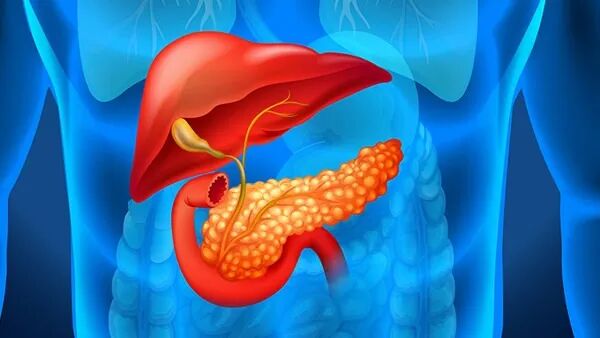

胰腺炎

慢性胰腺炎是胰腺癌的重要危险因素,持续的炎症状态加速了胰腺细胞的恶性转化。